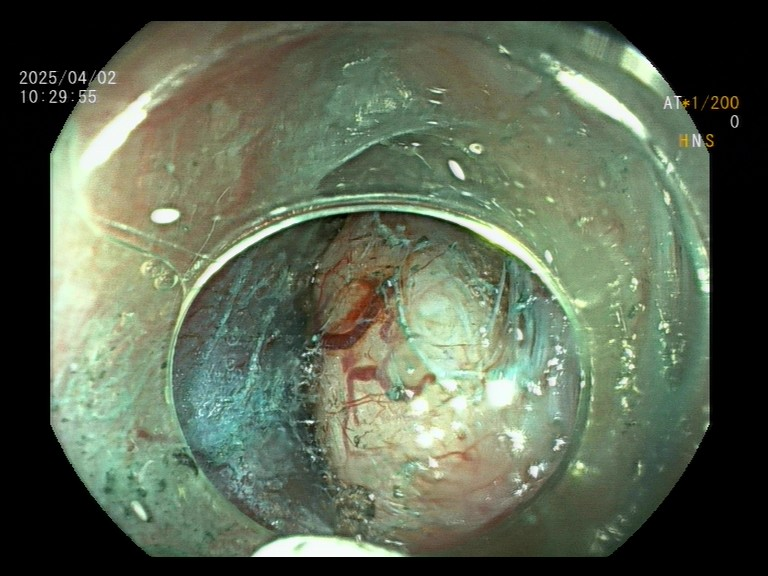

手术中食管粘膜下隧道内剥离,外侧就是主动脉弓 术后,患者感慨道:“真没想到这么大的肿瘤,手术后喉咙只有轻微异物感,24小时后就能喝水了!”最终病理报告显示肿瘤完整切除且边缘阴性,宣告此次手术取得圆满成功。 超微创技术:开启生命救治新篇章 相较于传统手术,此次运用的STER超微创技术优势显著: 1.体表零创伤:手术全程仅通过口腔自然腔道完成,体表不留任何切口,极大减轻患者心理与生理负担; 2.功能保全性强:完整保留食管结构与神经功能,有效避免术后反流等常见并发症,最大程度保障患者生活质量; 3.恢复速度惊人:术后1-2天患者即可进食流质食物,4-5天便能康复出院,恢复周期较传统术式缩短80%; 4.经济负担减轻:显著降低住院费用,切实缓解患者经济压力。 专家下沉赋能:筑牢区域健康防线 此次手术是重庆市“三甲医院专家驻点帮扶”项目的生动实践。重庆市人民医院依托医联体单位对口支援机制,在涪陵区人民医院建立起四级手术质控体系,让消化道肿瘤、贲门失弛缓症等疑难病症患者无需奔波,在家门口就能感受省市级医院的优质诊疗服务。 于劲主任表示:“我们将持续定期到涪陵区人民医院消化内科开展指导工作,确保复杂消化内科疾病得到规范、及时的治疗,让更多高难度内镜手术在‘家门口’就能顺利完成。”随着ESD(内镜粘膜下剥离术)、EUS(超声内镜)等前沿技术的不断下沉推广,越来越多复杂病例将通过内镜微创手术重获新生。 涪陵区人民医院消化内科/内镜室,门诊开设消化道早癌咨询服务,除基本的胃肠镜检查(检查时间周一至周五全天,周六上午半天,70岁以下无严重内科疾病可胃肠镜检查连做)外,还开展特色诊疗: 1.色素+放大胃镜(食管、胃、大肠早癌筛查); 2.消化道息肉、腺瘤、粘膜下肿瘤、早癌等内镜下切除(EMR、ESD、STER、EFTR)等; 3.内痔出血/脱出经内镜治疗(硬化剂+套扎); 4.消化道狭窄扩张/支架(食管、大肠)置入; 5.消化道异物取出; 6.消化道出血内镜治疗; 7.肝硬化食管静脉曲张套扎/硬化术(EVL/EVS); 8.经内镜胃造瘘,肠梗阻导管置入术等。 涪陵区人民医院消化内科温馨提示:吞咽梗阻、胸骨后疼痛等症状,可能是食管良恶性肿瘤的早期预警信号。随着内镜技术的飞速发展,90%以上的消化道黏膜下肿瘤可通过内镜微创手术实现根治。因此,一旦出现相关症状,建议及时进行胃镜检查,做到早发现、早诊断、早治疗。 |